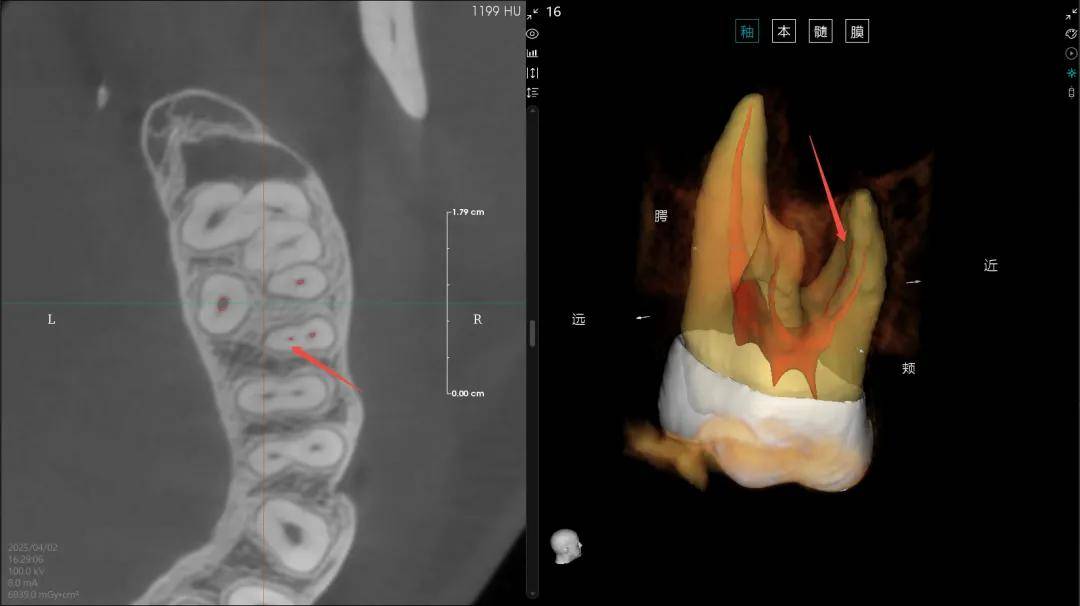

(4)“髓易诊”功能精准度与使用体验再提升,根管弯曲度支持手动/智能测量;髓腔提取算法迭代,识别准确率大幅飙升;新增牙体360°环绕观察,全方位掌控解剖细节,让根管诊疗更精准、更高效。

【▲算法优化前后MB2病例展示(优化后)】